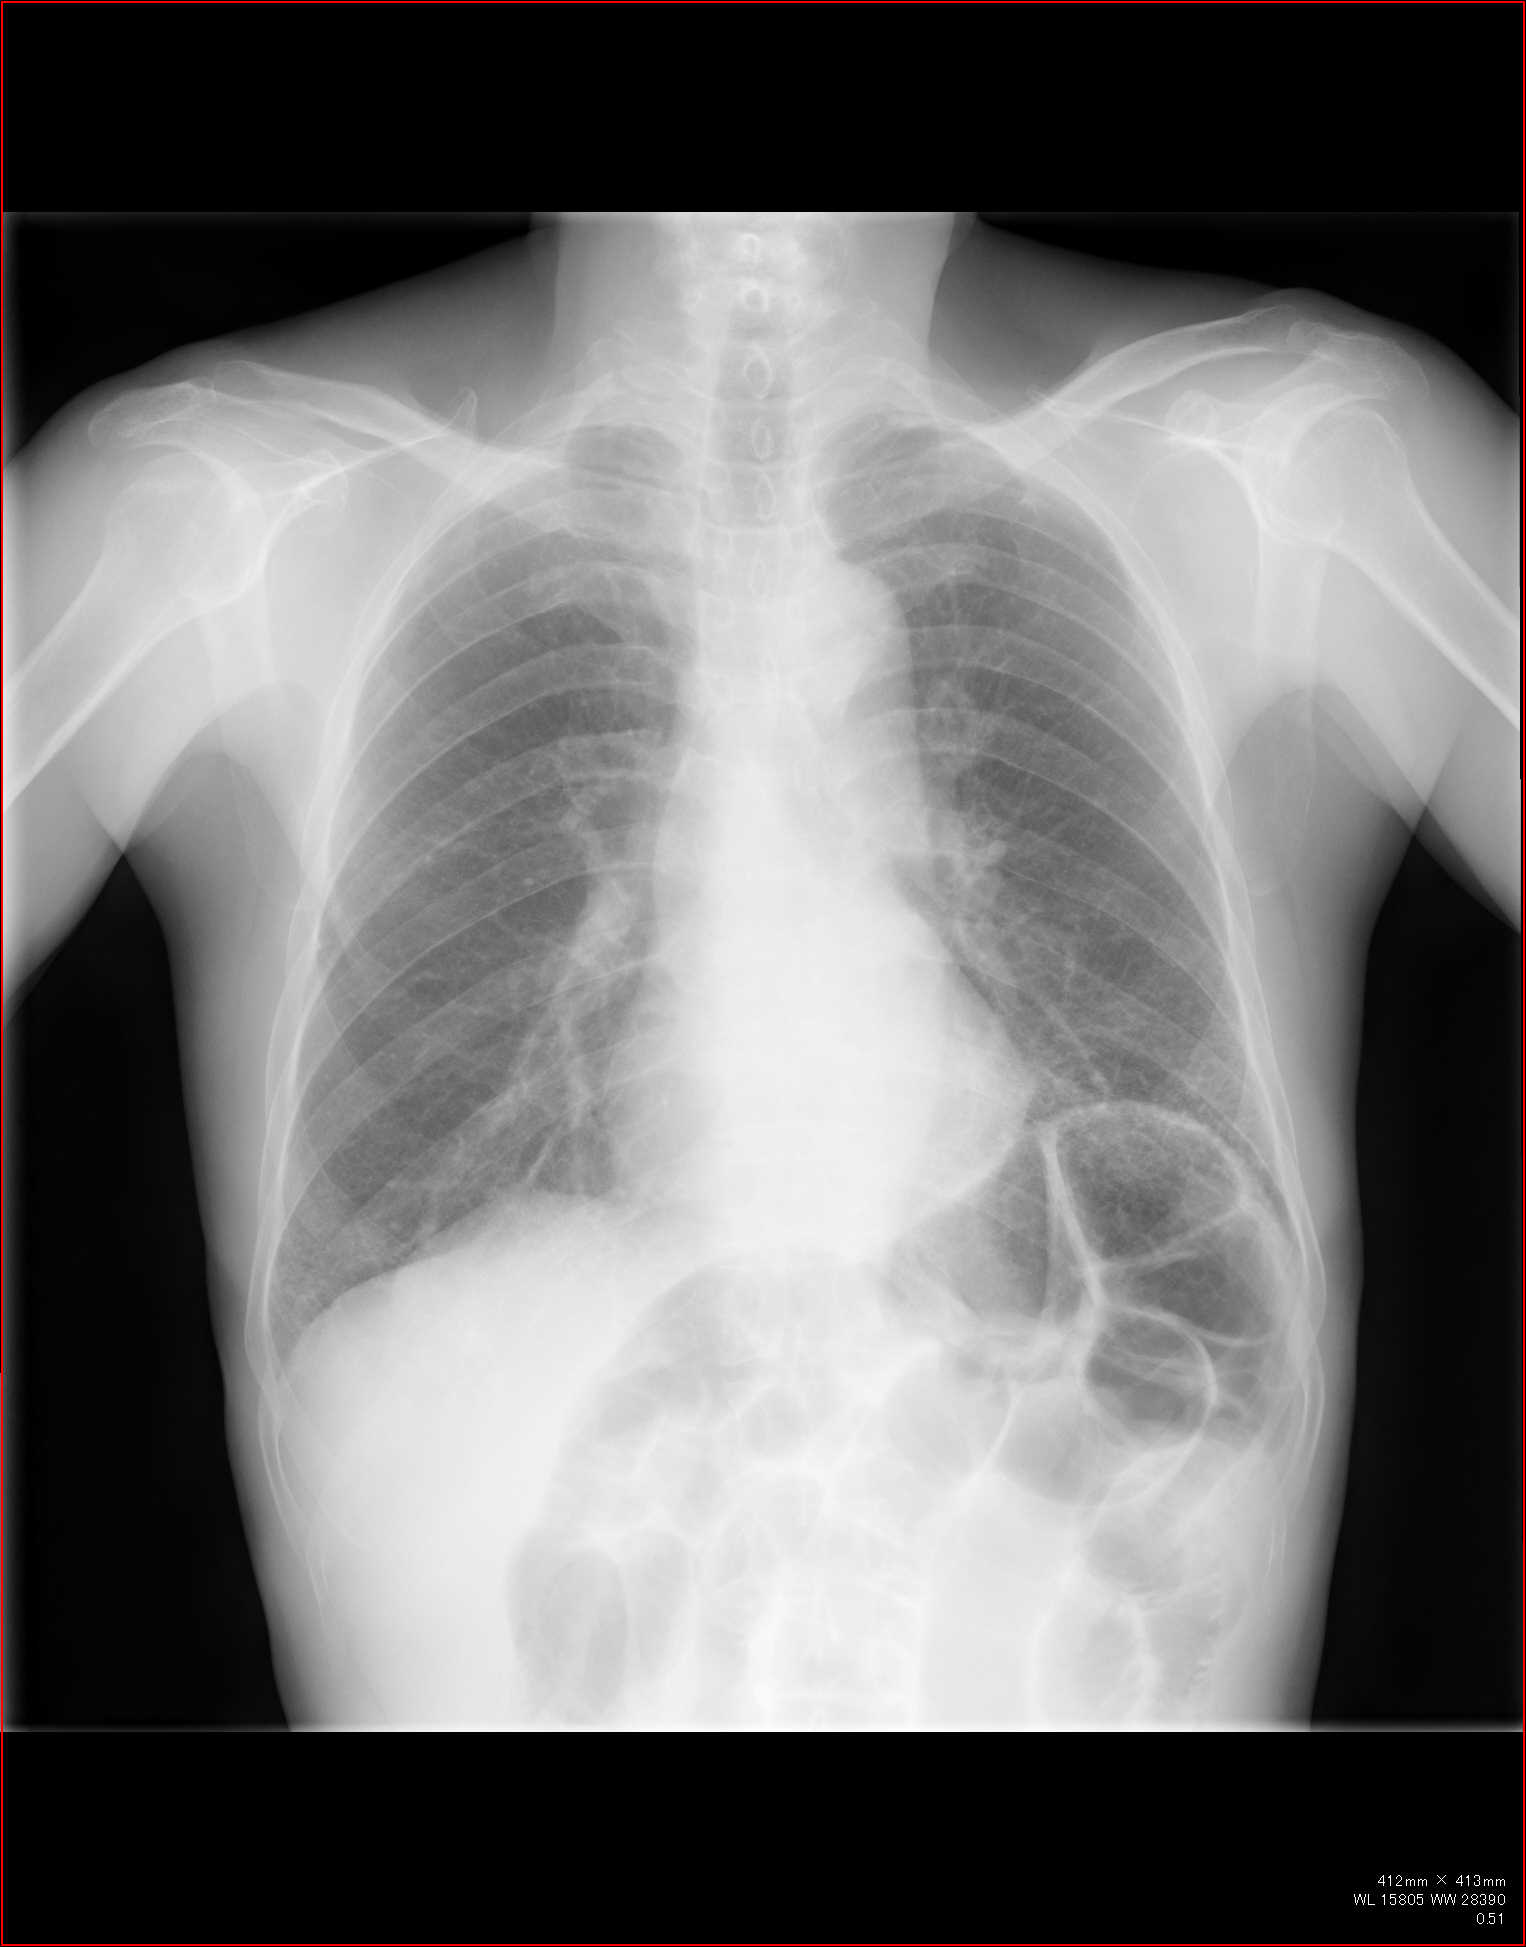

例えば肺の大きさ。

volume

lossや反対に過膨張などの所見は、圧倒的に胸部正面写真がわかりやすいですね。